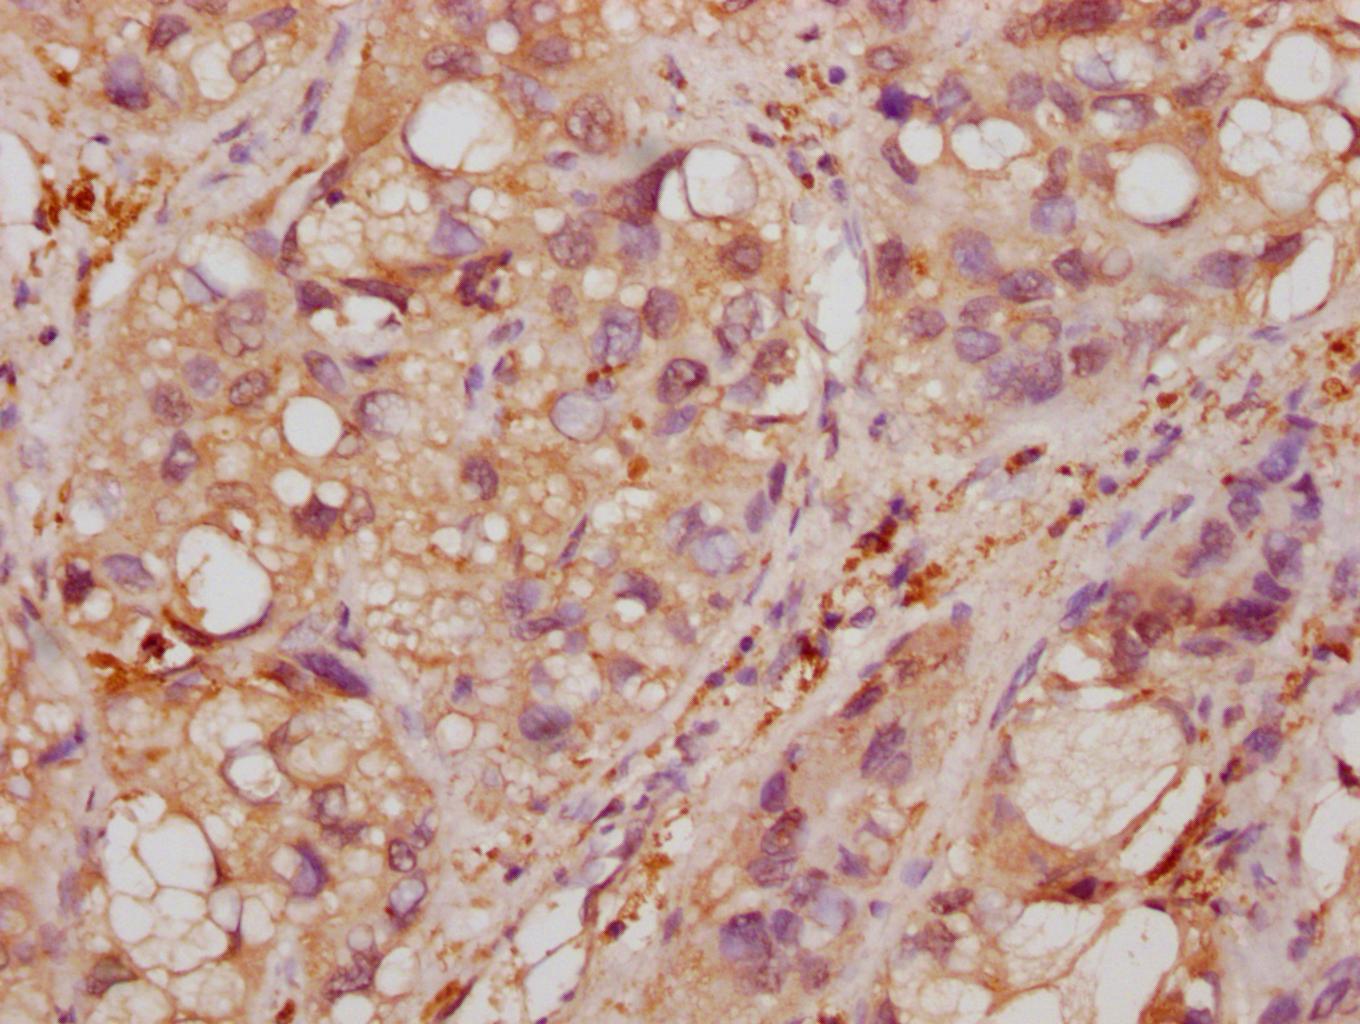

IHC image of CSB-MA007670A0m diluted at 1:500 and staining in paraffin-embedded human colon cancer tissue performed on a Leica BondTM system. After dewaxing and hydration, antigen retrieval was mediated by high pressure in a citrate buffer (pH 6.0). Section was blocked with 10% normal goat serum 30min at RT. Then primary antibody (1% BSA) was incubated at 4°C overnight. The primary is detected by a biotinylated secondary antibody and visualized using an HRP conjugated SP system.

-